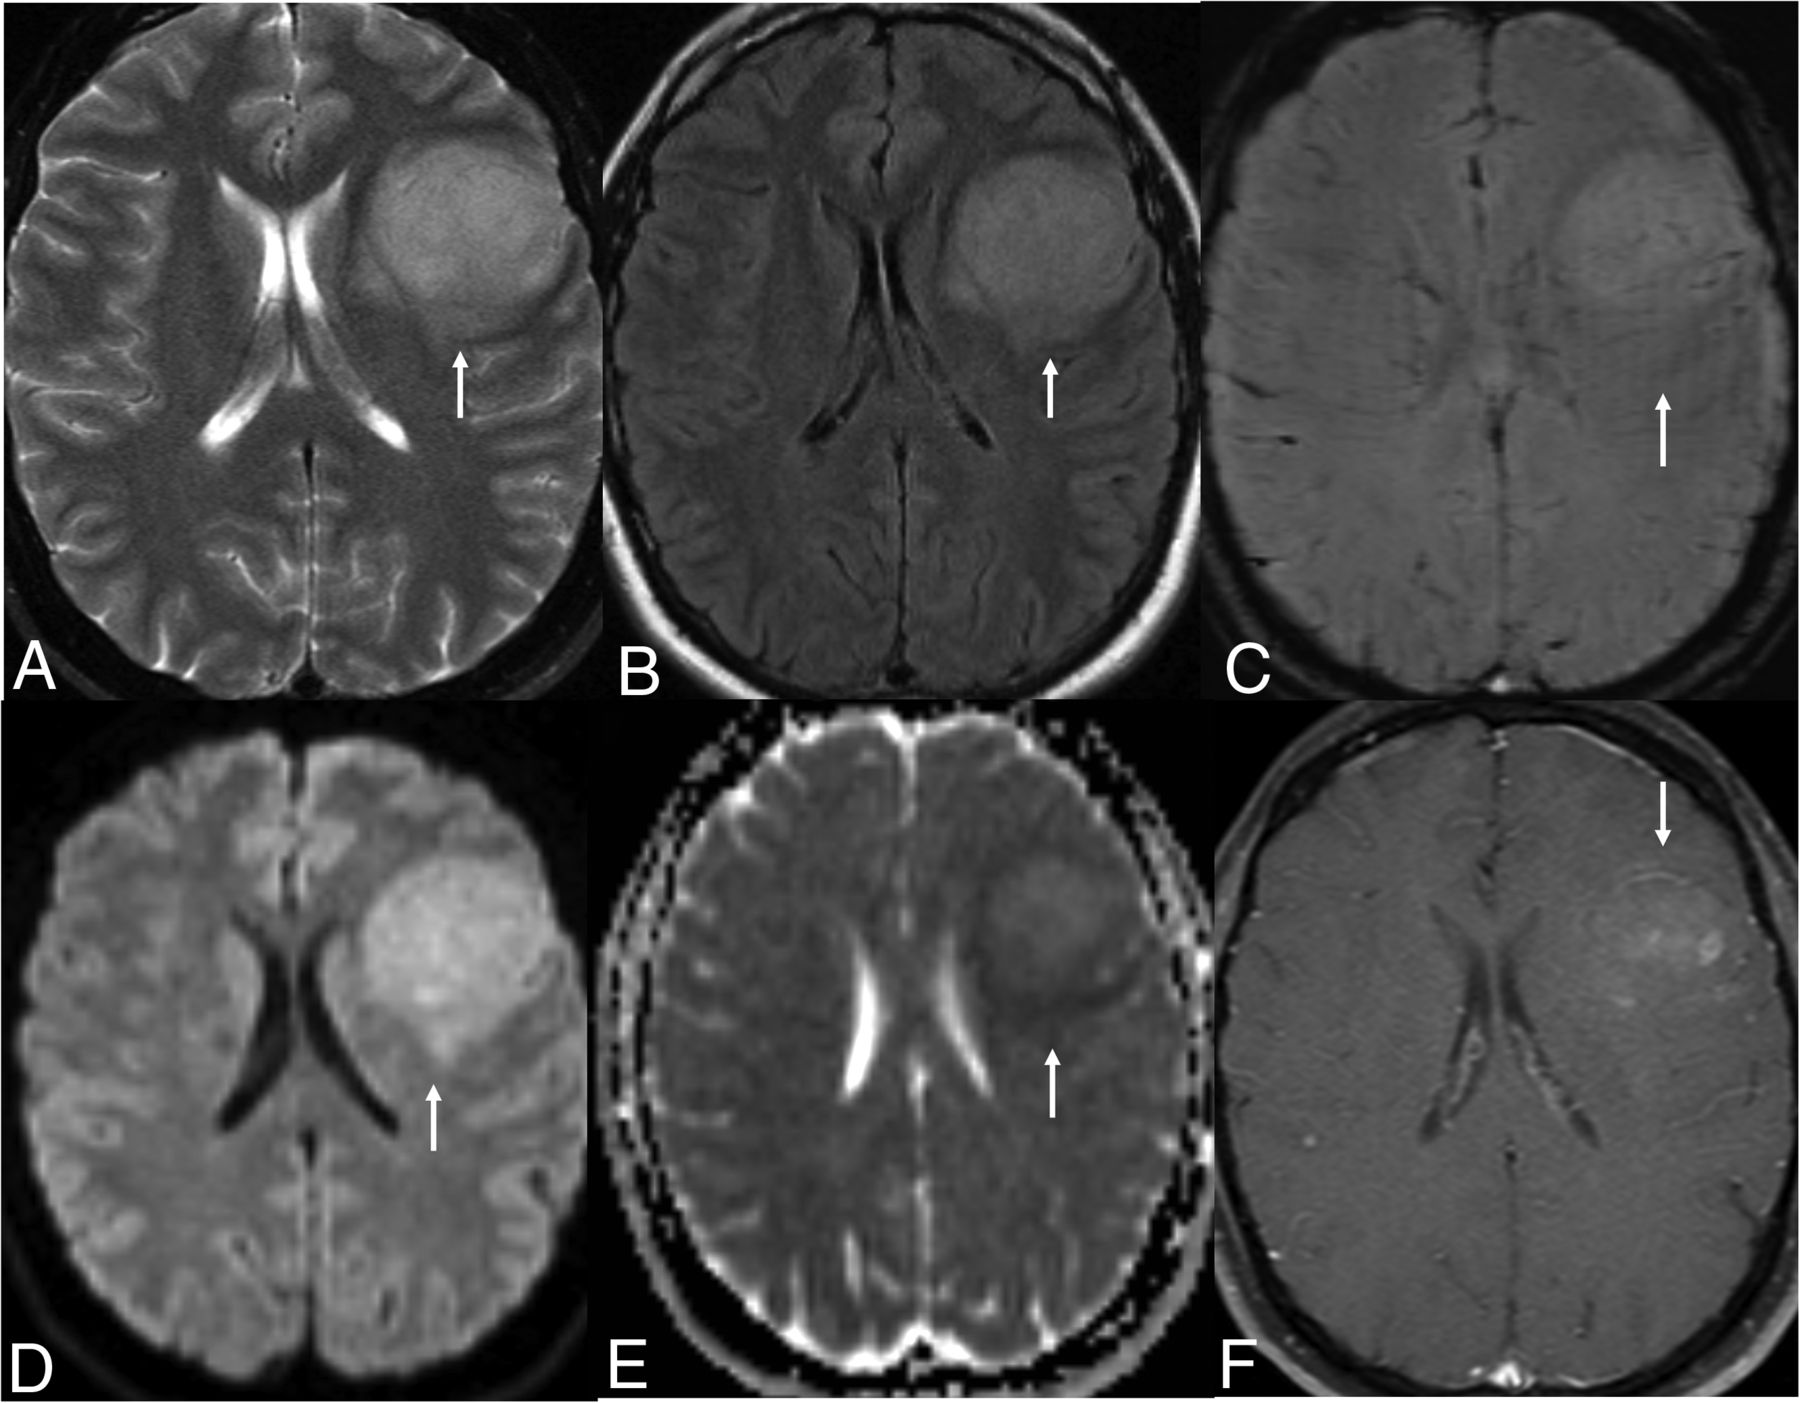

MR imaging revealed a large heterogeneous T2-signal cortical-subcortical mass centered in the left frontal operculum with areas of necrosis evident on T2-weighted image (Fig 3A). Multiple foci of petechial hemorrhage were seen within the mass on SWI with no areas of restricted diffusion/low ADC. Contrast-enhanced images revealed thick irregular peripheral enhancement with nonenhancing areas of central necrosis (Fig 3B). There was moderate surrounding perilesional edema with mild mass effect and midline shift. The primary radiographic differential was high-grade glioma, likely GBM. Metastasis was felt to be unlikely in the absence of any underlying malignancy and given the solitary nature of the mass.

Left frontal lobe mass in a 65-year-old woman with characteristic MR imaging and histopathological features of glioblastoma, IDH-wild-type (CNS WHO grade 4). Axial T2-weighted (A) and contrast-enhanced (B) images reveal a heterogenous T2-signal cortical-subcortical mass centered in the left frontal operculum with areas of necrosis and heterogeneous peripheral enhancement. H&E slide reveals the classic “pseudopalisading” necrosis characterized by a “garlandlike” arrangement of hypercellular tumor nuclei (C, arrows) lining up around a central clear zone of tumor necrosis (C, arrowhead). Microvascular proliferation is noted with delicate capillary-like microvessels resembling classic angiogenesis, multi-layered stratification of the endothelial cells and occlusion of the vessel lumen (D, arrows). The infiltrating glioma cells were negative for IDH1-R132H and for H3 K27M on immunohistochemistry. Chromosomal microarray analysis was performed by the by using molecular inversion probes on a whole genome array revealing genomic alterations include loss of 2q22.1 (including LRP1B), 2 copy gain of chromosome 7, loss of 9p21.3 (including CDKN2A and CDKN2B), and loss of 10p15.3p11.1. Tumor tissue was negative for MGMT promoter methylation. Final integrated diagnosis was “Glioblastoma, IDH-wild-type (CNS WHO grade 4).”

Histopathological examination by using H&E and immunohistochemical stains revealed a high-grade infiltrating glioma with marked nuclear atypia, high cellularity, brisk mitotic activity, MVP, and palisading necrosis, histologically corresponding to a high-grade infiltrating glioma (Fig 3C, -D). The tumor was negative for IDH1-R132H, had retained ATRX expression, and was positive with glial fibrillary acidic protein (GFAP). Ki67 showed a high level of labeling and p53 was positive only in a subset of cells. Genomic alterations on chromosomal microarray included loss of 2 copy gain of chromosome 7, focal homozygous loss of 9p21.3 (including CDKN2A and CDKN2B), and loss of 10p15.3p11.1. Tumor tissue was negative for MGMT promoter methylation. Final diagnosis based on histopathological and molecular features was GBM, IDH-wild-type (CNS WHO grade 4).